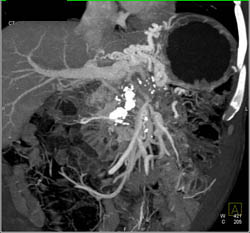

Chronic Pancreatitis With Encased PV/SMV